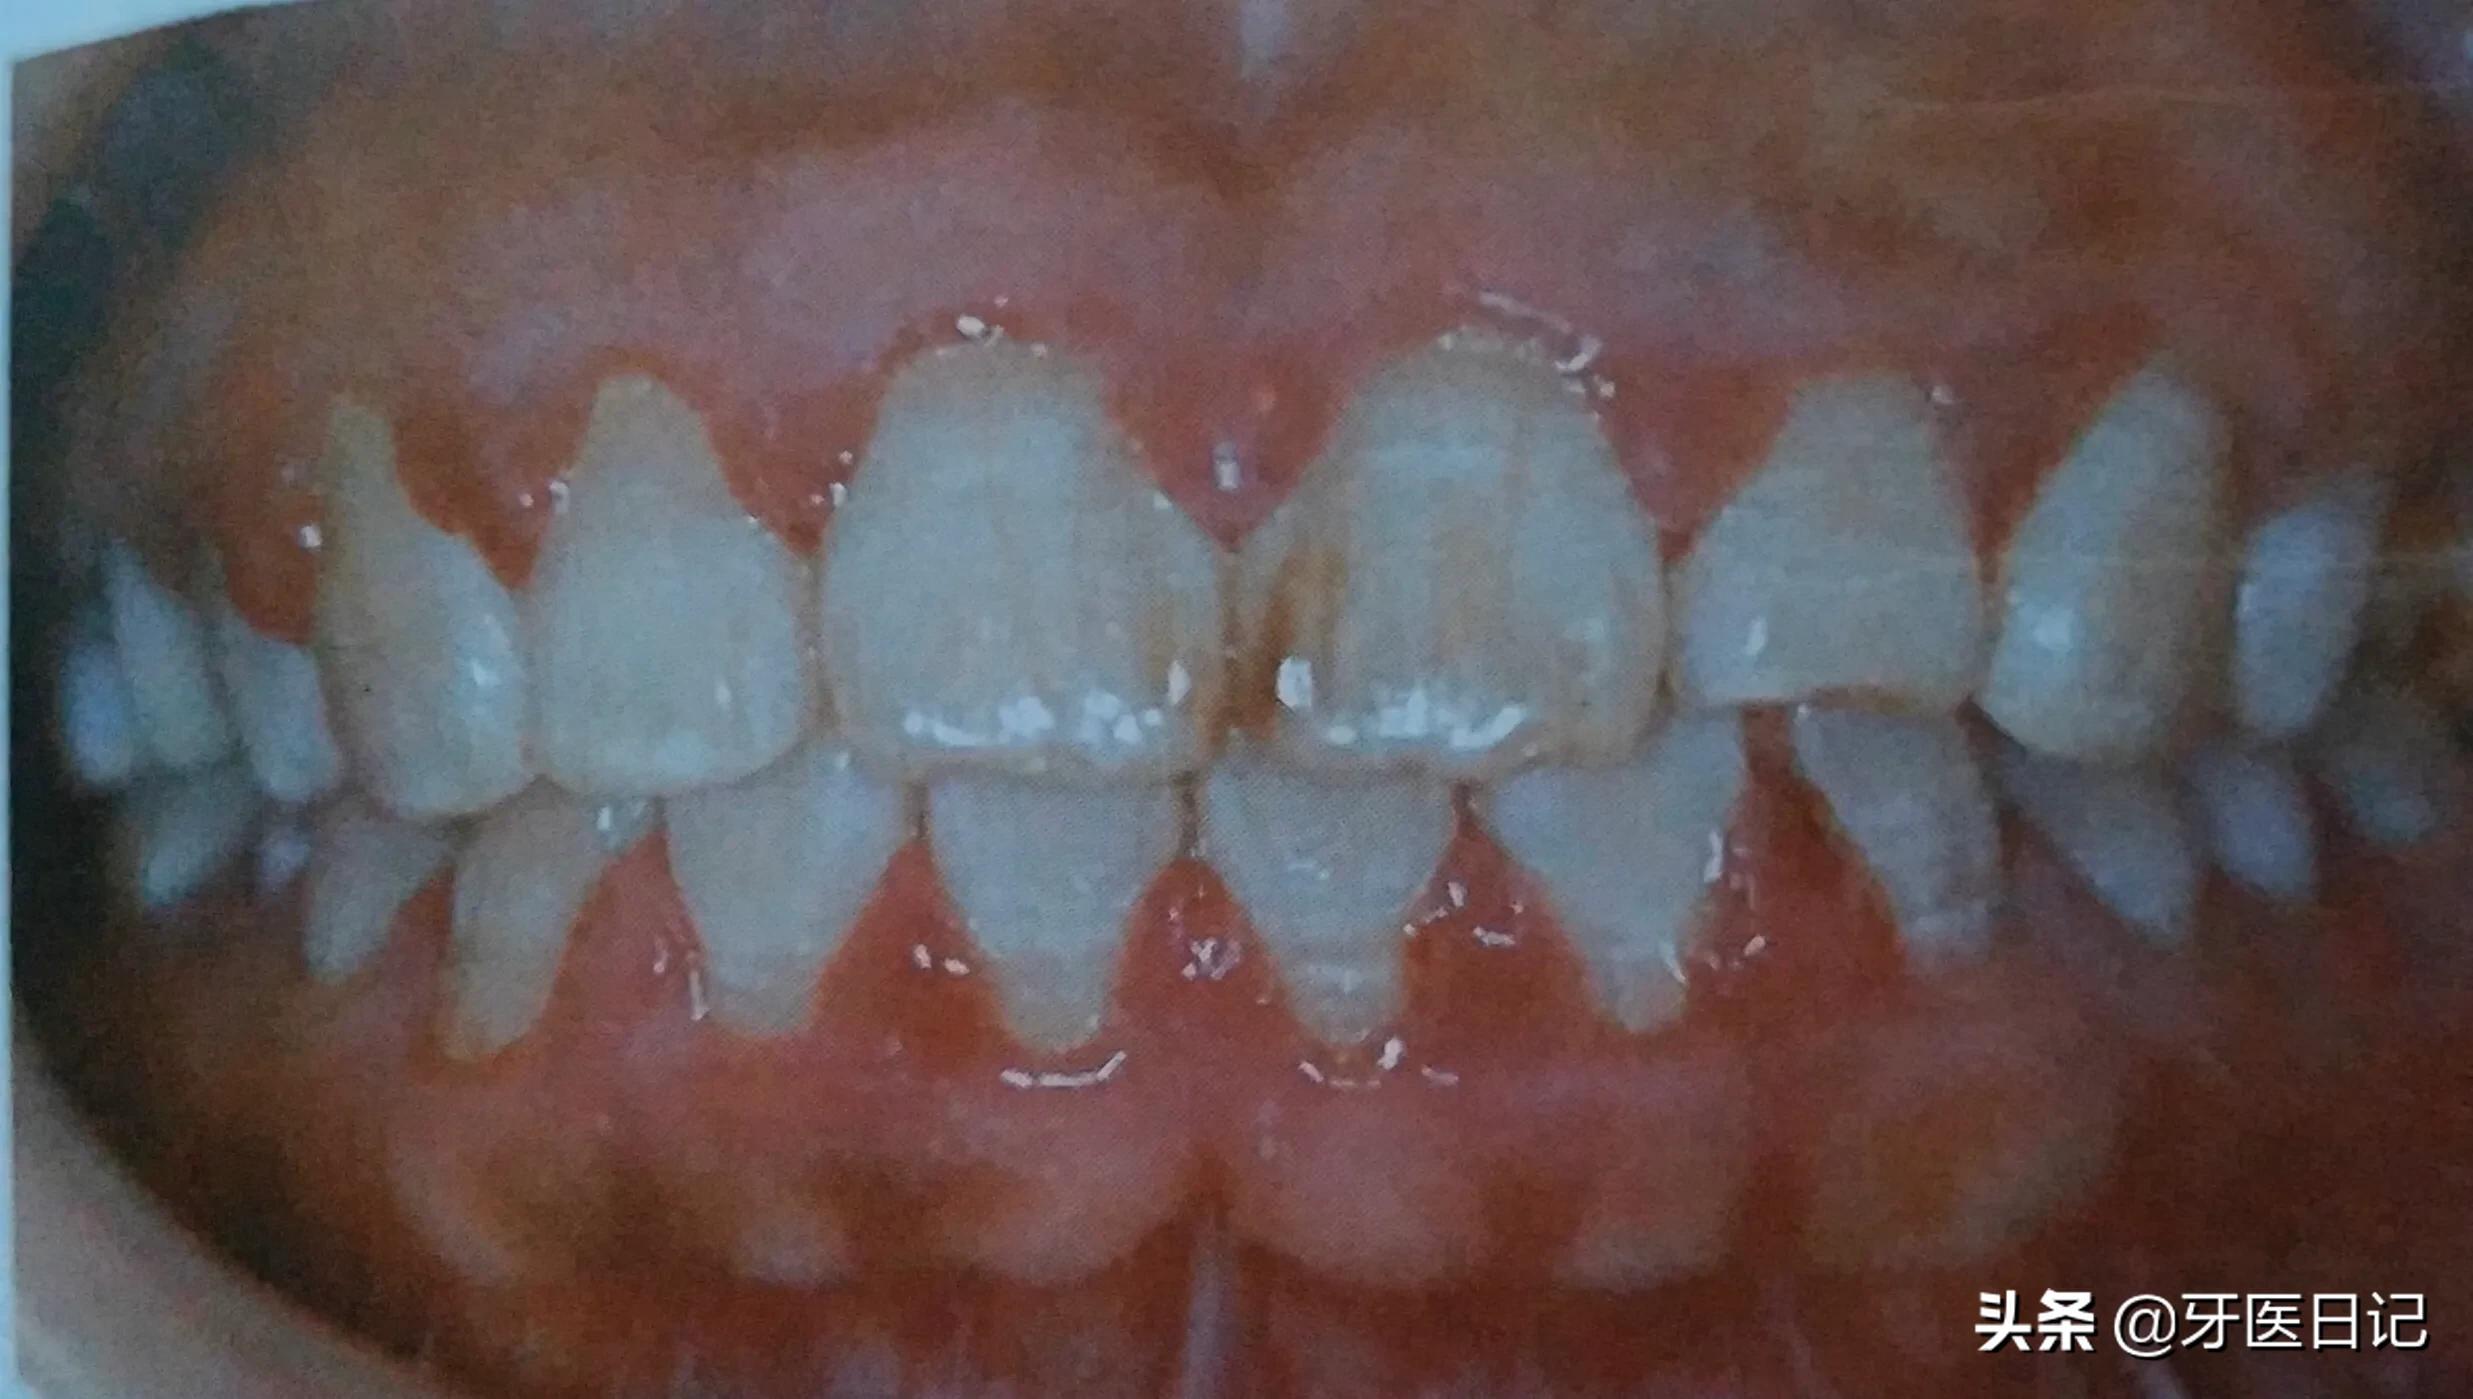

首先就是牙龈的红肿、出血(刷牙时、咬硬物时),其次还有牙龈溢脓、糜烂等

①牙龈的炎症:主要表现为牙龈出血,可以表现在刷牙时、咬东西时、严重者可在无任何刺激的情况下出血。

最常见的是口腔卫生不洁,有牙结石的存在,牙结石压迫刺激牙龈,导致牙龈红肿、出血,特别在青春期的同学,或者孕期的女性常会因激素水平的改变而出现青春期牙龈炎和妊娠期牙龈炎,其主要表现就是牙龈红肿和出血,而普通人的牙龈红肿出血多是牙结石刺激导致,当然一些系统疾病也会导致牙龈出血,如白血病。